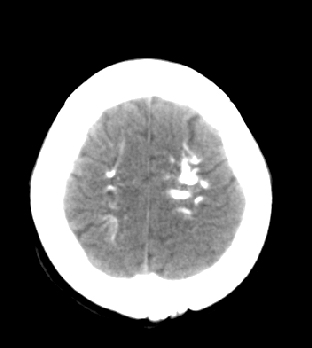

女性 38岁 病人脚弓反张 8岁以后不能行走 今年查pth11.9ng/ml(正常28ng/ml)

这么弥漫的钙化还第一次见。

考虑甲状旁腺功能减退症,该病是因甲状旁腺激素分泌减少或功能障碍所引起的少见病。其特点是低血钙,高血磷,且血pth极低。因低钙常可引起神经精神激惹症状,包括手指,趾,口角麻木,严重时可出现肌肉痉挛,喉哮鸣和惊厥,甚至癫痫样发作,有的可出现抑郁症及精神失常。长期的高磷血症可引起脑内结构对称性多发性钙化,特别是小脑和基底节的钙化可致锥体外系症状,而钙化的ct表现为类似于脑出血的密度增高影。

鉴别诊断:fahr 病,又称特发性家族性脑血管亚铁钙沉着症,是一种少见病,男女发病无显著差异,多为散发。临床表现为阵发性意识不清,首发症状开始于14~51 岁不等,以后呈阵发性发作,表现为突然神志丧失、跌倒、四肢抽搐约,发作后常表现为意识淡漠,性格改变,血清钙在正常范围。ct表现尾状核头呈倒“八”字形或片状钙化,在大脑半卵圆中心皮、髓质交界处多为点、小片状钙化,丘脑多呈对称小点、小条状钙化,小脑齿状核呈括弧形或不对称性小片状钙化。

原发性甲状旁腺功能减退症和fahr病都有神志上的改变等症状,且头颅ct检查均可见颅内出现钙化。但fahr病无pth低下,ct表现钙化影在大脑半卵圆中心皮髓质交界处、丘脑、小脑齿状核等处。 而甲状旁腺功能减退症pth极低,ct虽可见钙化影,但部位在小脑和基底节等处。